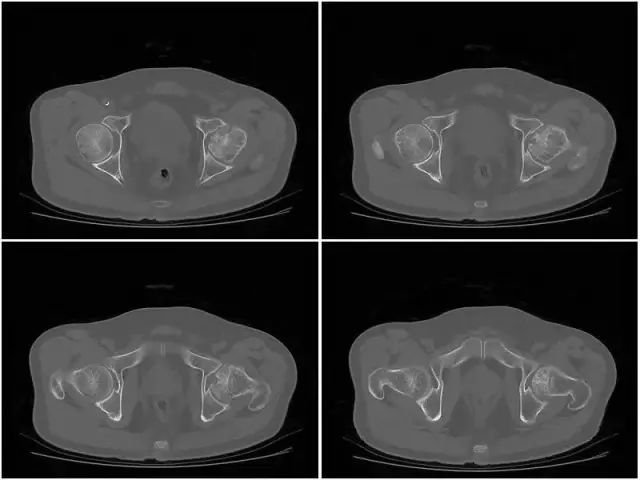

股骨头坏死CT的表现

Ⅰ期 骨质无明显异常,但可有滑膜增厚,关节囊肿胀,关节腔积液,关节间隙相对增宽。

Ⅱ期 股骨头形态正常无塌陷,正常时股骨头中心因持重应力的作用骨小梁生理性密度增高呈“星芒征”,当发现骨缺血性坏死时,星芒状骨纹间骨小梁吸收呈不均匀大眼状,由于反映性增生,使星芒状骨纹增粗、扭曲、浓密。

Ⅲ期 此期称为塌陷前期,股骨头变平,股骨头前上部关节面下见窄细状透亮带,即“半月征”。

Ⅳ期 股骨头塌陷变形,股骨头内是不同程度囊变,周围有硬化或不规则,因塌陷所致的浓度区,可见碎骨片和关节游离体。继发退行性骨关节病,出现增生骨刺、关节间隙狭窄、关节半脱位。

上图为IV期